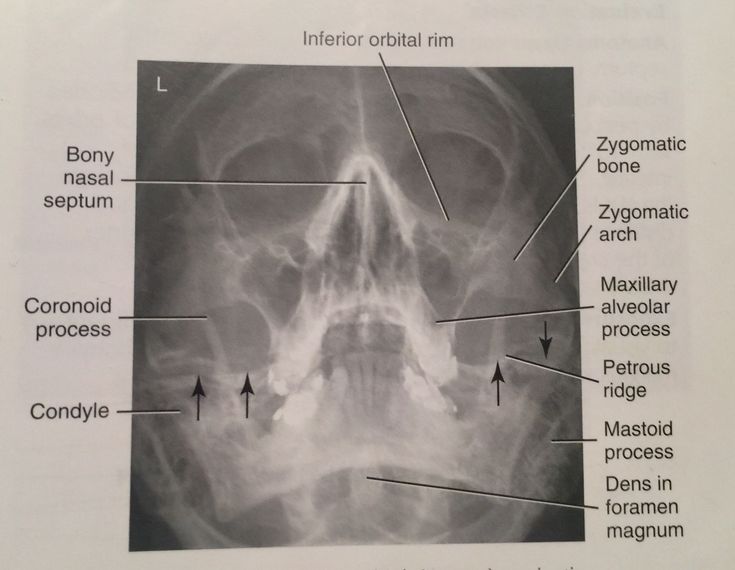

Parietoacanthial (Waters)

Part Position: Chin on IR; MML perpendicular; OML forms 37° angle with IR.

Central Ray: Perpendicular to exit at acanthion.

Collimation: 10×10